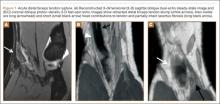

Physical examination revealed distortion of the biceps with a palpable defect in the right elbow consistent with a complete biceps tendon rupture. This was confirmed on MRI, which showed avulsion of the distal biceps tendon from its insertion on the radius. There was 4 cm of proximal retraction of the tendon, which was kept at the level of the joint line by a partially intact lacertus fibrosis (Figure 1).

For 7 days after surgery, the patient wore a posterior elbow splint in a flexed, supinated position. Afterward, rehabilitation initially consisted of passive ROM progressing to active ROM at postoperative week 4. Pronation was slow to return, but essentially full ROM was regained by 7 weeks after surgery. Seven weeks after surgery, a radiograph showed a small amount of HO near the radial tuberosity (Figure 3A). However, the patient was clinically progressing well, and by 9 weeks was comfortably performing slow, controlled arm curls with a 10-lb weight. Despite the clinical improvements, MRI 9 weeks after surgery showed high-grade partial-thickness retearing of the distal biceps tendon without significant retraction. With dynamic MRI, it was evident that the focus of HO near but external to the distal tendon entered the radioulnar space on pronation (Figures 3B–3D). On axial images of the center of the cortical tunnel, the short-axis diameter of the heterotopic bone measured 2.5 mm, and the bone clearly was occupying part of the radioulnar space during pronation. As the patient was not having pain and was increasing in strength, the clinical team resumed rehabilitation, albeit at a gentler pace.